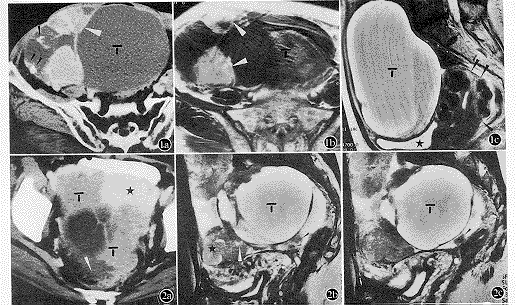

摘要 目的 探讨CT和磁共振成像(MRI)在原发性卵巢癌分期中的价值和限度。方法 收集42例原发性卵巢癌患者的临床资料,对照手术和病理,获得CT、MRI、CT加MRI各自的准确性、敏感性、特异性(简称三特性)及术前分期。结果 CT和MRI对评价子宫受侵和子宫直肠窝病变均较满意(三特性均≥80% )。CT在判断单侧或双侧卵巢肿瘤和腹膜种植性病变方面优于MRI,主要是敏感性较高;MRI则在显示包膜受侵或破裂、侵犯除肠管以外的盆腔脏器、子宫直肠窝病变以及淋巴结转移方面优于CT,三特性多数较高。CT、MRI及CT加MRI的分期准确性分别为73.7%、68.4%及70.6%(P>0.05)。对于多数部位病变的诊断,两者均显示特异性较高而敏感性偏低。结论 CT和MRI是原发性卵巢癌术前分期有效的影像学方法。

【Abstract】 Objective Toinvestigate values and limitations of CT and MRI applied in staging of patients withprimary ovarian carcinoma (POC). Methods Forty two patients with POCproven by radical surgery, laparotomy, and postoperative pathology were studied. Incomparison to surgical and pathological findings, sensitivity, specificity, and accuracyof CT, MRI and CT plus MRI were calculated. Staging by the three imaging methods wasobtained according to FIGO′s classification. Results CT and MRIshowed higher accuracy in evaluation of invasion to uterus (89.5% and 94.7%) and diseaseof Douglas pouch (94.7% and 97.4%). CT was to some extent superior to MRI in assessingipsilateral or bilateral tumor and lesions related to peritoneal seeding; MRI, however,had better capability of diagnosing invasion to ovarian capsule, pelvic organs excludingbowel, nodules in Douglas pouch, and metastasis to lymph nodes. The overall accuracy ofstaging by CT, MRI, and CT plus MRI was 73.7%, 68.4%, and 70.6%, respectively (P>0.05).Conclusion CT and MRI are useful imaging modalities in staging of POC,but low sensitivity for detecting involvement in some anatomic regions needs to beimproved.